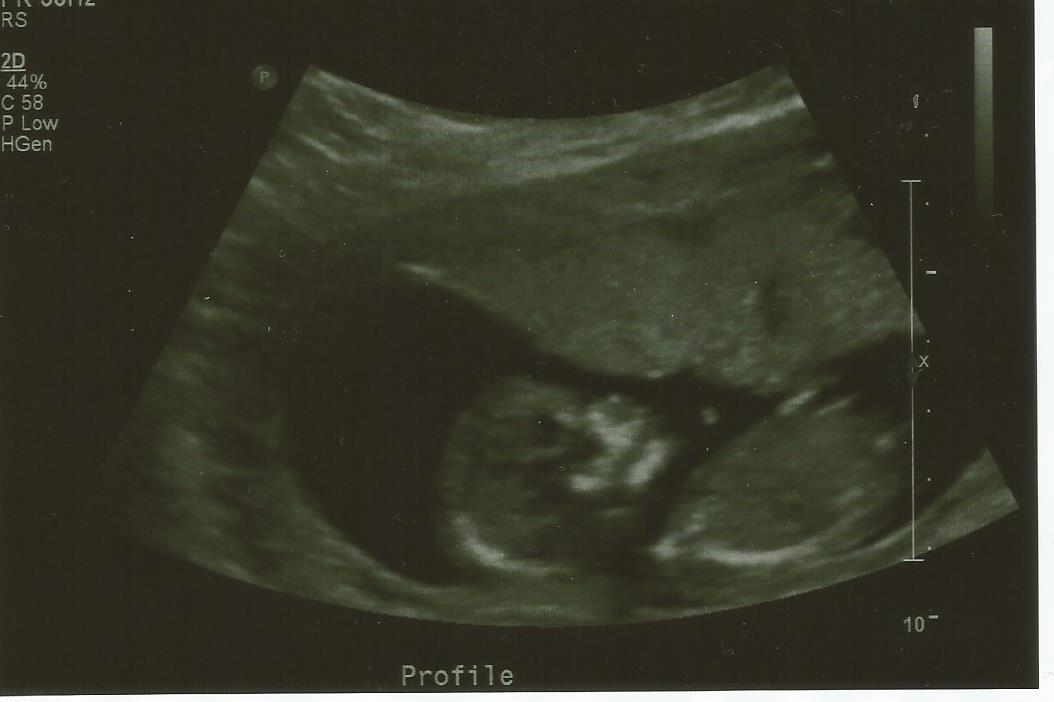

I don't want to know until I deliver in Jan. this scan is 13 weeks 4 days.Attachment 36984